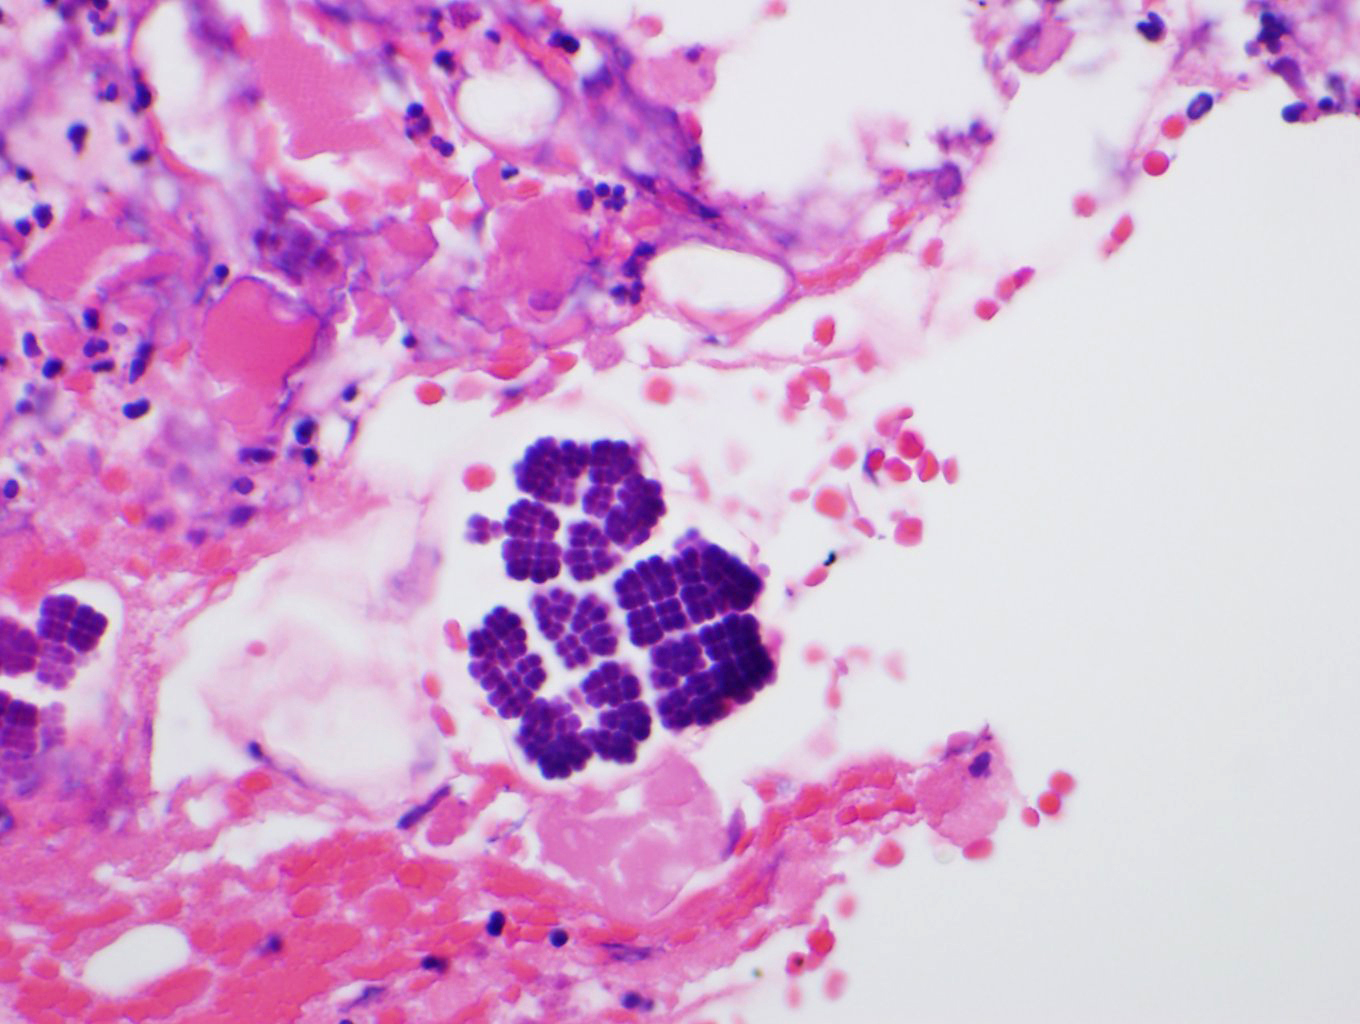

The entire ulcer was submitted for microscopic examination. No malignancy or H. Pylori identified. However, multiple bacterial cocci were noted at the ulcer bed. They are basophilic-stained and cuboid-shaped bacteria that arranged in tetrad packets, consistent with Sarcina ventriculi.

Sarcina ventriculi is anaerobic gram-positive coccus that grows in an acidic environment. It is typically diagnosed with a hematoxylin-eosin stain and, if needed, with a Gram special stain. It was first described by Goodsir in 1842 as a human pathogen. The pathogenic status of Sarcina in human is still unclear. However, association of Sarcina with a patient with gastric perforation, emphysematous gastritis, and peritonitis as well as occurring in the background of gastric adenocarcinomas has been reported. It can normally be found in the soil and air, where it can survive for years by forming spores at alkaline pH. It ferments Carbohydrate as an energy source. Sarcina species, whose natural habitat is the soil, is probably ingested with soil particles present in the food. Various reports in veterinary literature have implicated the Sarcina species in the development of gastric dilatation and death in livestock, cats and horses.

Differential diagnoses for S ventriculi are Sarcina maxima and Staphylococcus species. The most helpful feature in light microscopy to differentiate S ventriculi from S maxima is the thick extracellular layer present on the outer surface.